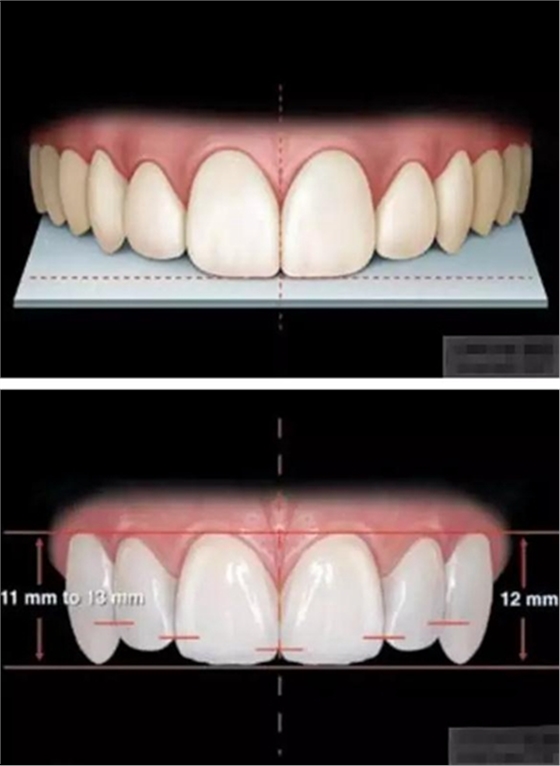

審美序列清單:

1、切牙的位置長(zhǎng)度

2.頜學(xué)

3.牙齒寬度

前牙的黃金分割比例

正面觀

側(cè)切牙約為中切牙的60%

尖牙約為側(cè)切牙的60%

4.牙齒比例

中切牙正常/理想的 寬/長(zhǎng)百分比約為75%—80%